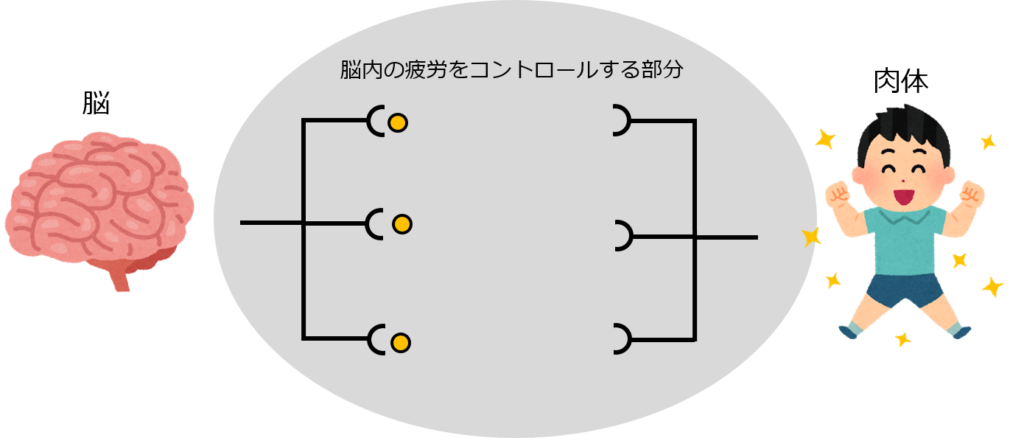

Operation Blue Wind 乱用 中毒 依存ってなに

Operation Blue Wind 乱用 中毒 依存ってなに